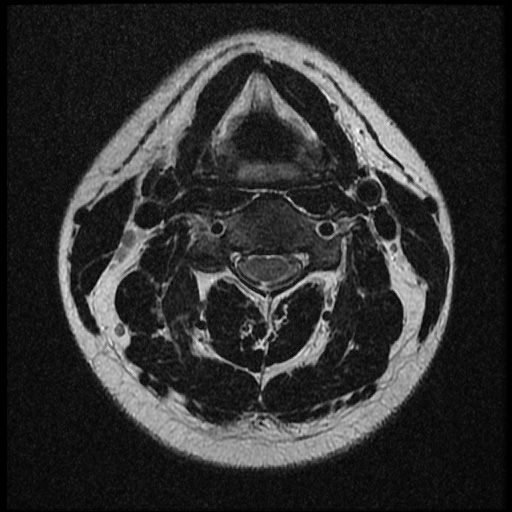

이 MRI 사진은 21년도 사고 당시 찍은 MRI 사진 입니다. 확인 부탁드립니다~

전체 mri를 다 봐여겠지만 보여주신 mri 컷에서는 의미있는 경추 디스크탈출이 보이지 않습니다.